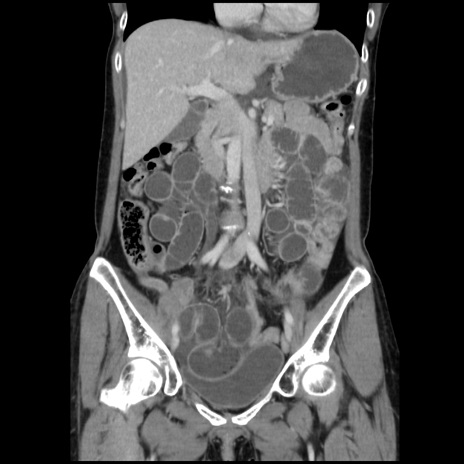

症例32(冠状断像)

【症例】40歳代 女性

【主訴】上腹部痛、嘔気・嘔吐

【現病歴】約9時間前頃から急に上腹部痛、嘔気、嘔吐が出現。改善しないため救急要請。

【既往歴】子宮頚癌(広汎子宮全摘術、放射線療法)、腸閉塞

【身体所見】腹部:平坦、軟、腸雑音亢進、上腹部を中心に腹部全体に圧痛あり。

【データ】WBC 8400、CRP 0.03